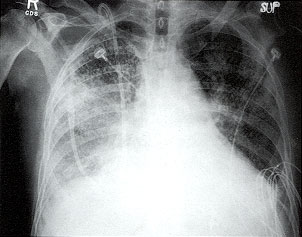

ผู้ป่วยปอดอักเสบจากเชื้อไวรัสชนิดรุนแรง จะพบมีฝ้าขาวที่ปอดข้างขวา |